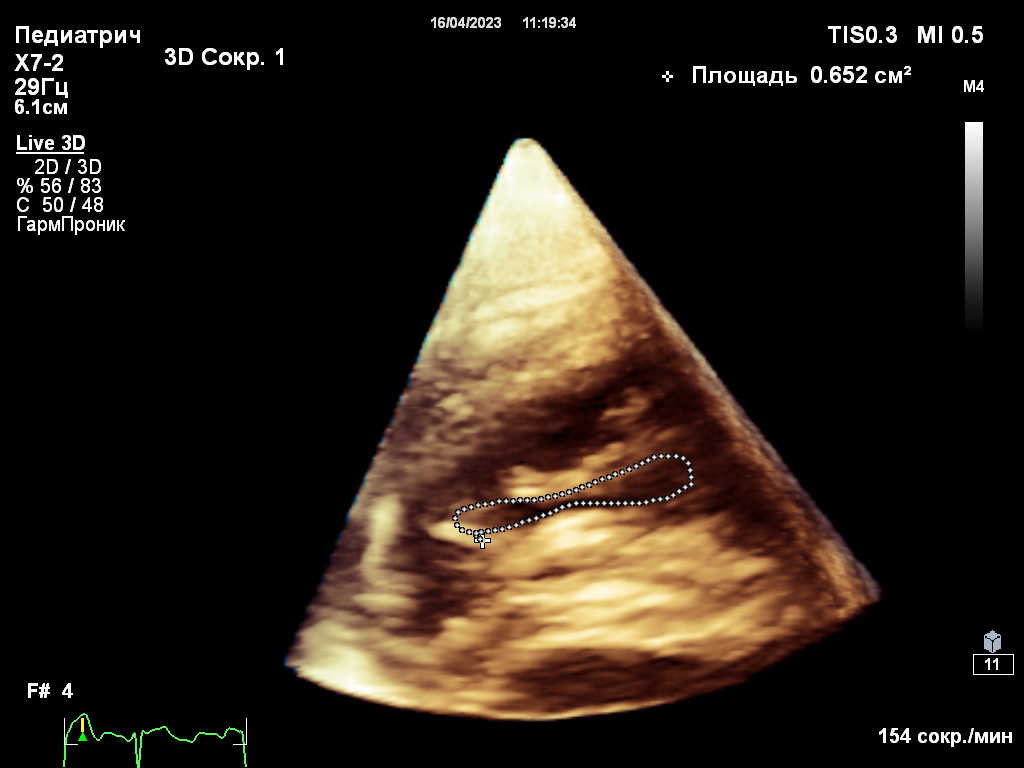

Собака находилась под наблюдением с 5-месячного возраста. При эхокардиографическом исследовании были выявлены следующие аномалии (фото 1-3):

Спустя 8 дней после проведения операции было выполнено контрольное эхокардиографическое исследование, результаты которого выявили следующие изменения (фото 6-8):- Конечный диастолический размер (КДР) правого желудочка снизился с 34 до 22 мм.

- Площадь регургитационного отверстия уменьшилась с 2,7 до 0,7 см2.

- Степень регургитации - moderat/severe.

- Отсутствие застоя в системных венах.

- Систолическая функция ПЖ – в пределах нормы.